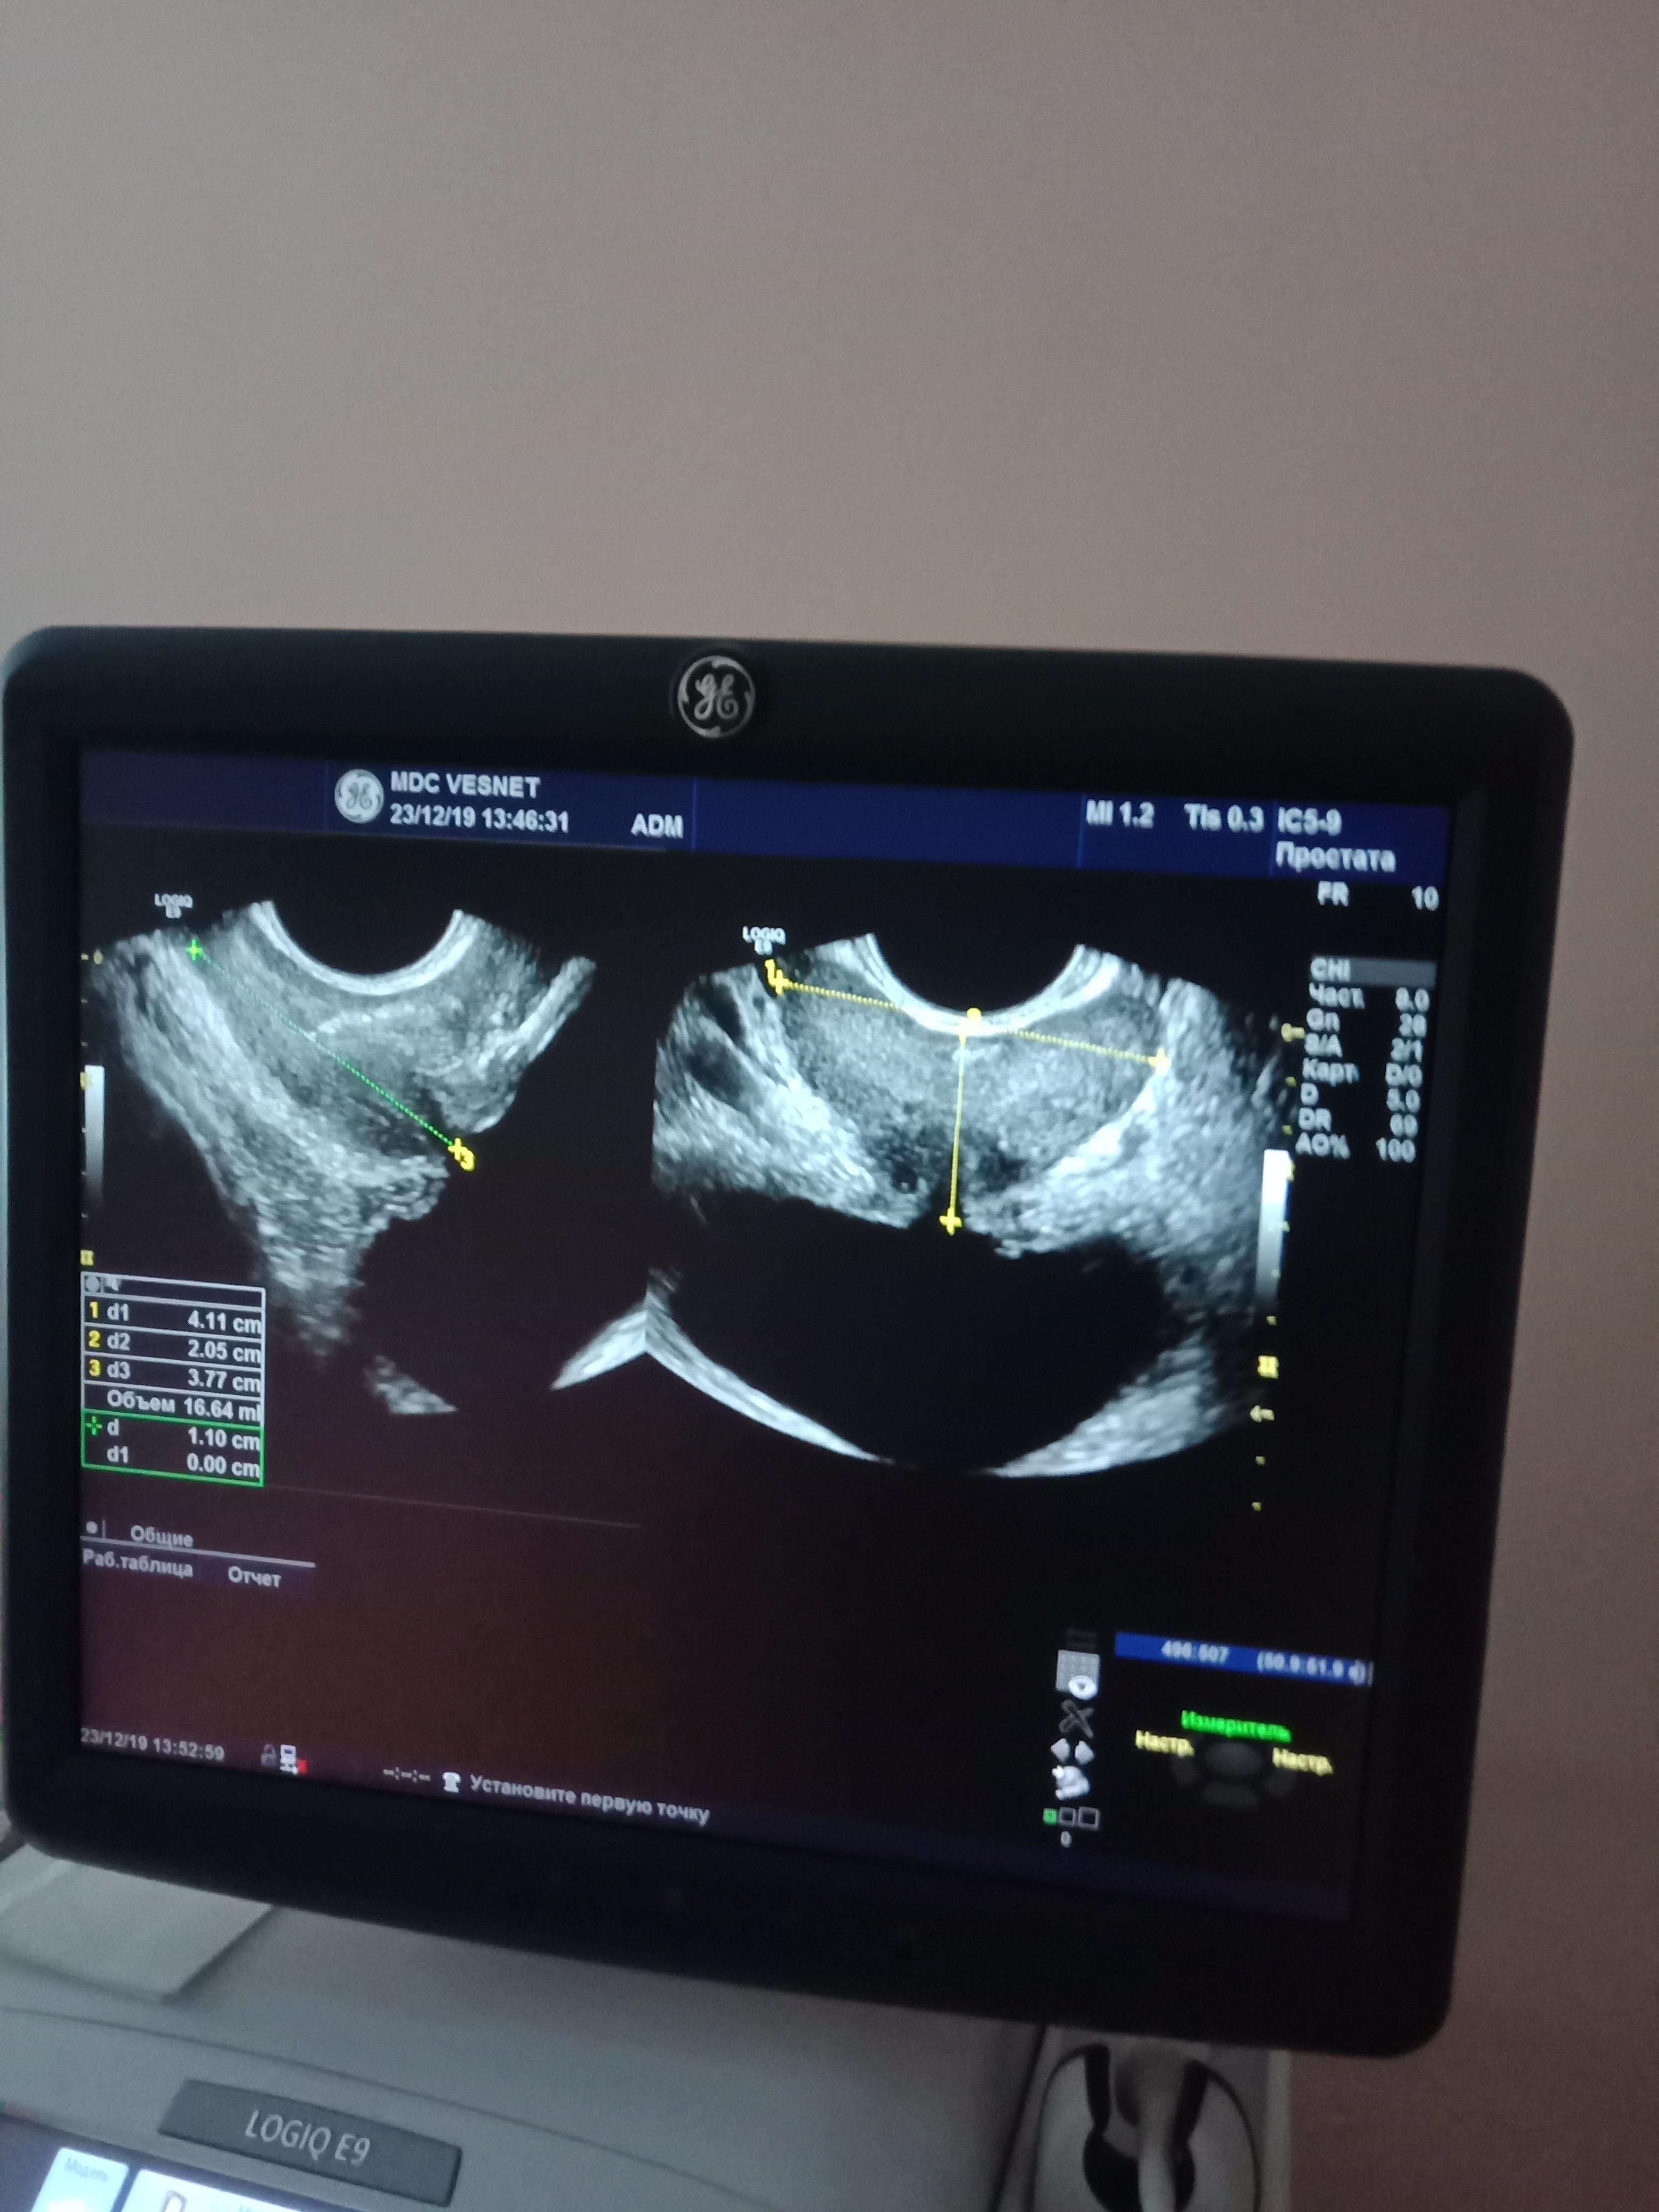

Здравствуйте, у меня такая проблема, иногда когда чихнешь или резко кашлянешь, сводит простату, иногда тянет яичко с права или скорей всего под ним, желаю узи, говорят все норм.

Здравствуйте! Сдайте эякулят на бакпосев и андрофлор. Сделайте УЗИ органов мошонки. С результатами посетите уролога очно Удачи!